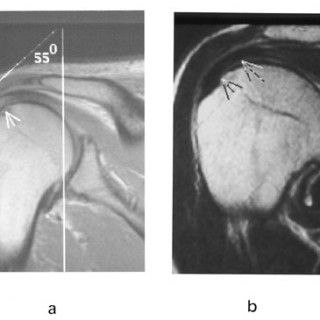

Magnetisk resonanstomografi, eller bare MR, er en teknikk som kan gi snittbilder av en hvilken som helst del av kroppen i en hvilken som helst retning. Teknikken benytter ingen ioniserende stråler, men baserer seg bl.a. på bruk av magnetfelter og radiobølger (1). Snittbilder kan gi god fremstilling av blodårer, men er utilstrekkelige for visualisering av tredimensjonal karanatomi. MR-angiografi (MRA) er en gruppe MR-teknikker som kan gi angiografiliknende, todimensjonale projeksjonsbilder av karanatomien. Det tredimensjonale kartreet kan betraktes fra valgfrie synsvinkler, hvilket gir et...